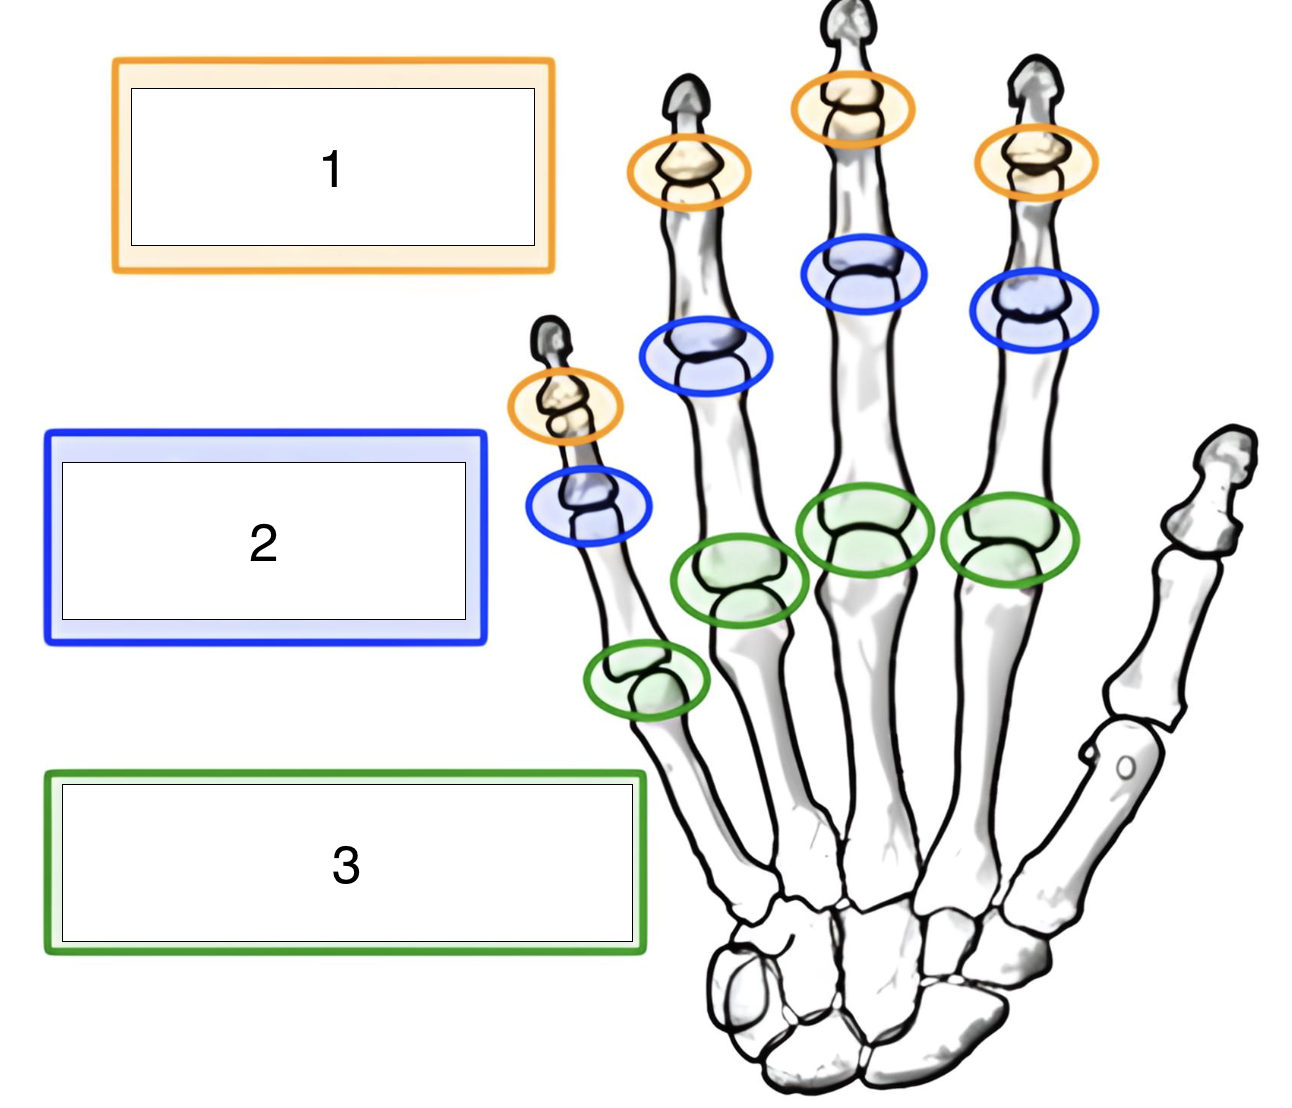

what is the highlighted joint (green, 3)?

metacarpophalangeal (MCP)

what is the highlighted joint (blue, 2)?

proximal interphalangeal (PIP)

what is the highlighted joint (orange, 1)?

distal interphalangeal (DIP)